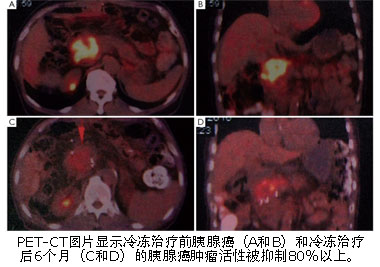

复大肿瘤医院医疗团队在复大肿瘤医院院长,国际冷冻治疗中心首席专家牛立志博士的带领下,采用CT引导下经皮冷冻治疗结合碘125粒子种植和免疫治疗,至今已成功治疗了265例胰腺癌患者,其中大部分病人患有III期或IV期的中晚期胰腺癌。有些患者在复大肿瘤医院接受治疗后已存活6年以上。复大肿瘤医院领先世界的治疗胰腺癌技术已经吸引了来自欧洲,美国,东南亚的很多胰腺癌病人前来诊治。

The majority of the patients suffering from pancreatic cancer present in the late stage of their disease and therefore have poor prognosis. Pancreatic Cancer metastasis usually occurs at early stage, any treatment would be regarded as palliative at this stage. In addition, less than 10% of pancreatic tumor can be surgically removed, and most pancreatic tumors are not responding to chemotherapy. Led by Dr Niu Lizhi who is Chief Specialist in International Cryosurgery Centre, medical teams in FUDA Cancer Hospital have so far treated 265 patients with pancreatic cancer, most of whom have stage III or stage IV of pancreatic cancers by using CT-Guided percutaneous cryosurgery in combination of Iodine 125 seed plantation and immunotherapy. Some patients have survived for more than 6 years after being treated in FUDA.